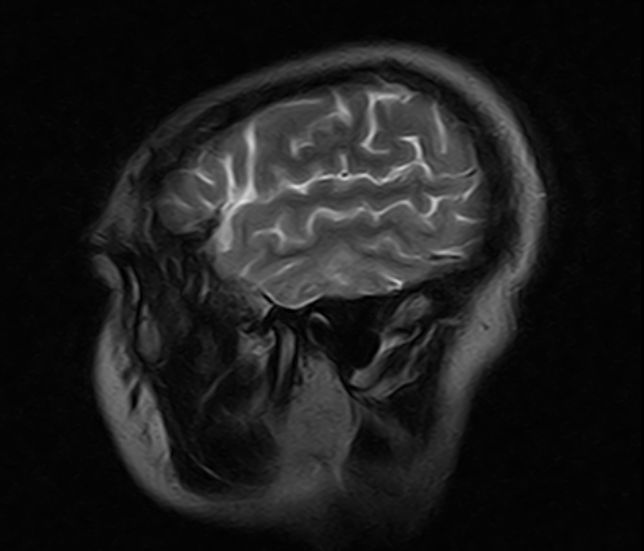

标题: MRI2379:30岁,男,癫痫10年,请各位看一下;CT示:左颞叶钙 [打印本页]

标题: MRI2379:30岁,男,癫痫10年,请各位看一下;CT示:左颞叶钙

考虑左侧颞叶脑血管畸形(avm)。----t1低等高混杂信号,t2等高信号周边较多流空血管影[冠状位明显],mra左侧大脑中动脉受压,远侧聚集.

考虑avm,建议行增强扫描,看供血a与引流v,以明确诊断。